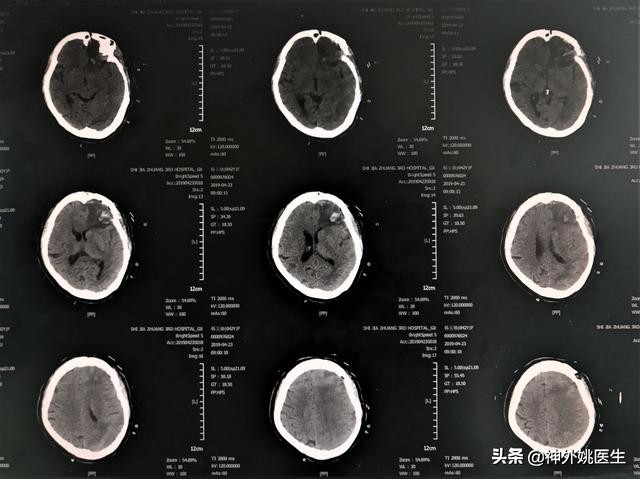

头CT检查:左额部占位,考虑脑膜瘤。(图1、2)

图1 左额部可见类圆形等密度影,大小约3.6cm x 3.9cm。

图2 左前颅底骨质凹凸不平,未见骨质明显破坏。